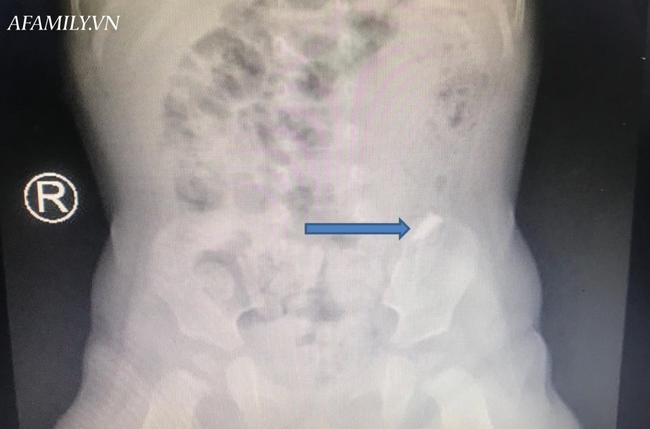

Ảnh chụp phim cho thấy dị vật nằm trong bụng bệnh nhi.

Các bác sĩ cho chụp X-quang bụng ngực và cho kết quả dị vật đi nhanh qua thực quản, dạ dày, môn vị, xuống tá tràng…

X-quang bụng được chụp mỗi 4-6 giờ để theo dõi sự di chuyển của dị vật để can thiệp phẫu thuật lấy dị vật nếu trẻ có tình trang đau bụng, xuất huyết tiêu hóa, thủng ruột.